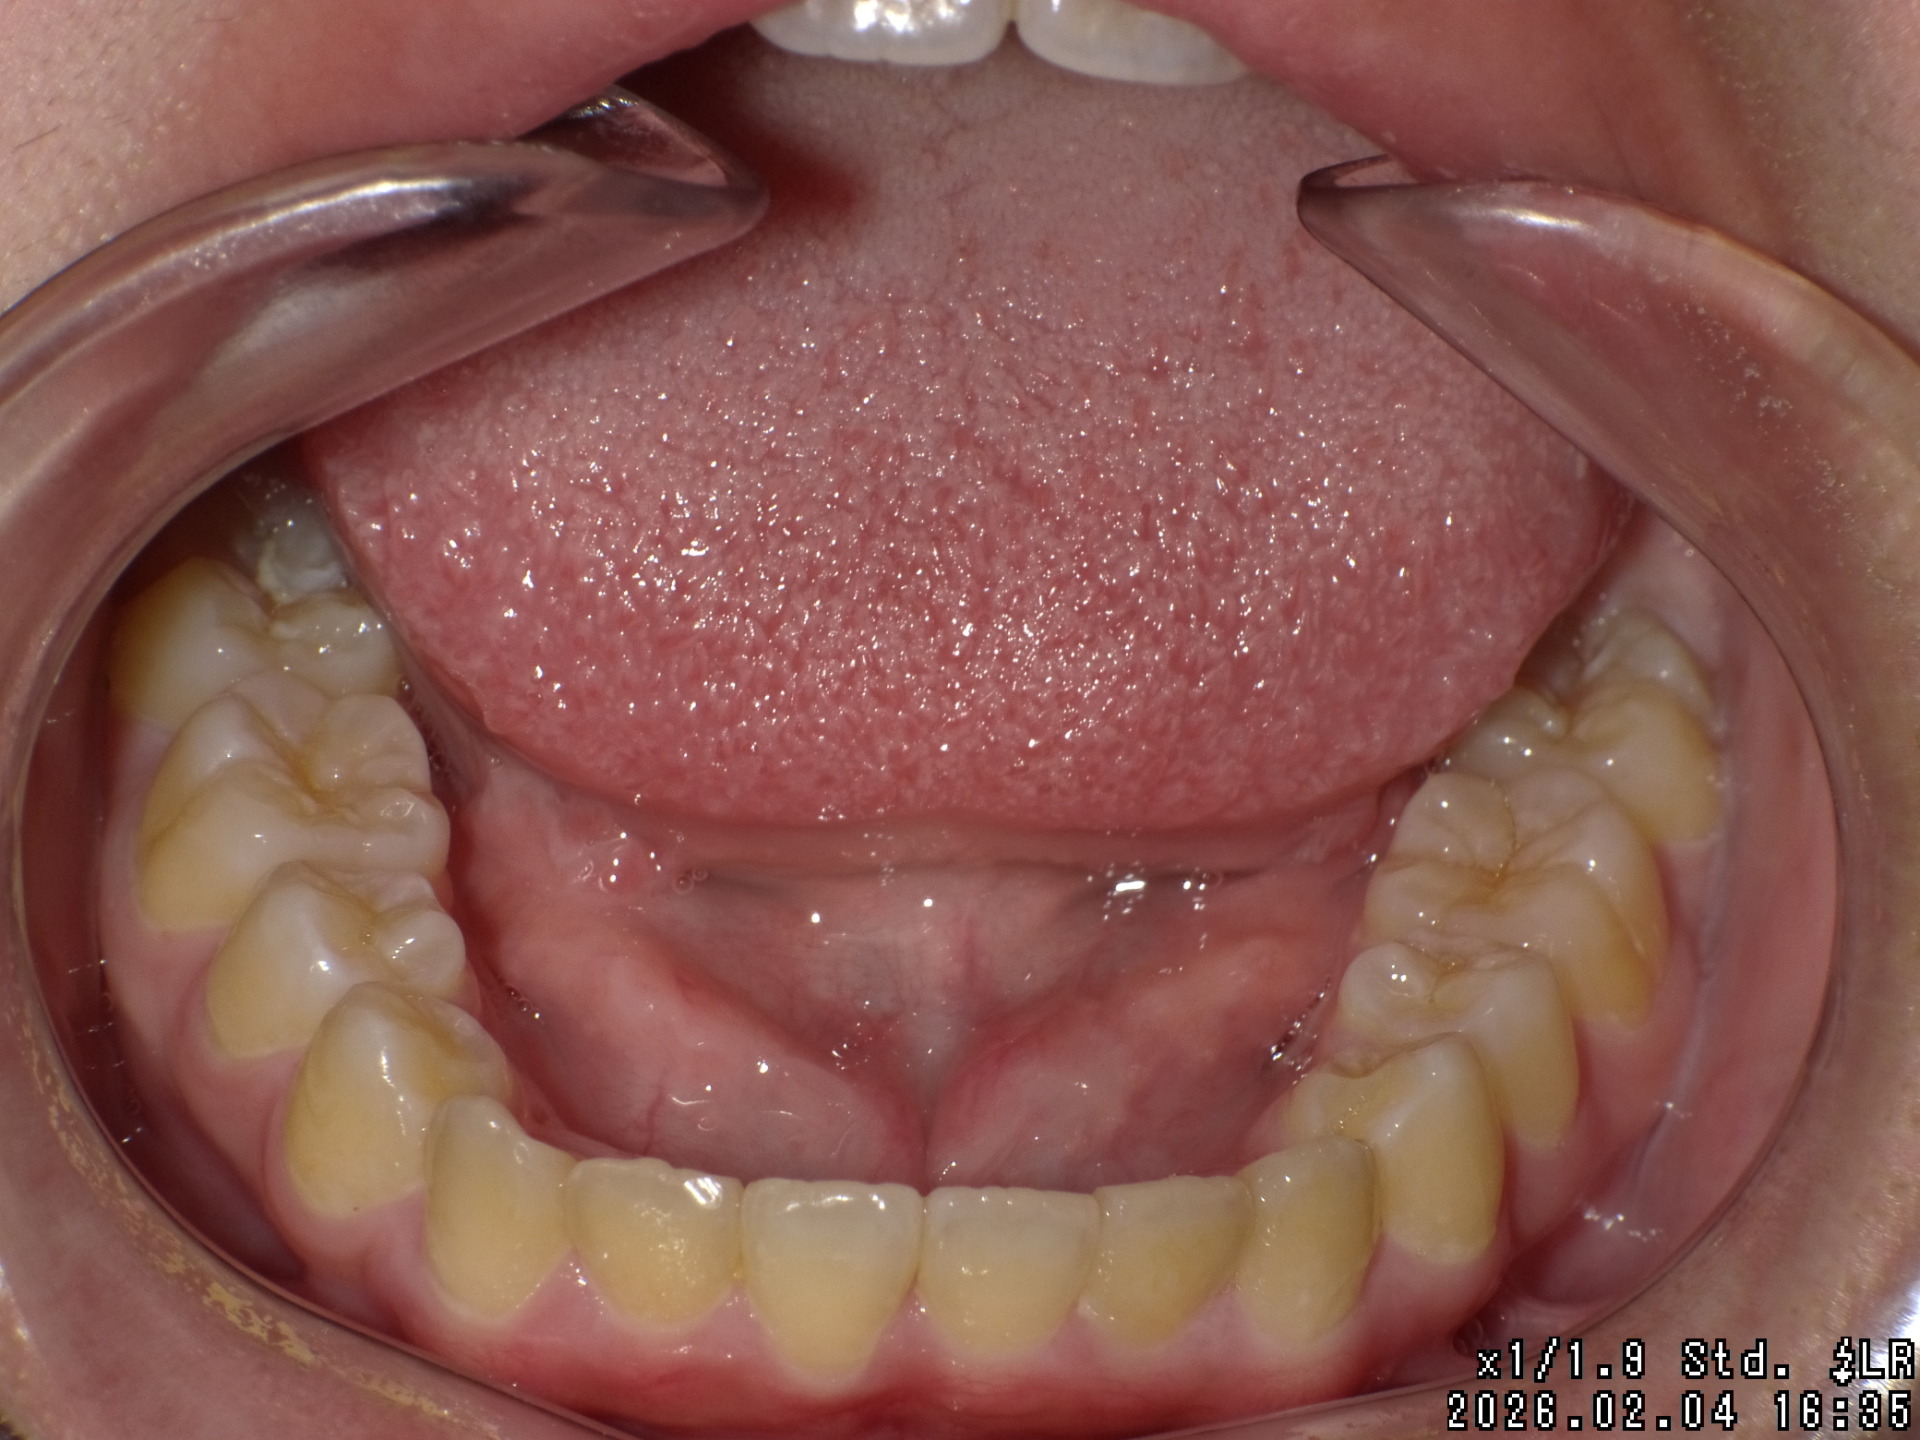

矯正前

| 症状 | 上顎前突 過蓋咬合 |

| 処置内容 | プレート拡大処置・ディスタライザー・インビザライン・オーソテイン・マルチブラケット装置 |